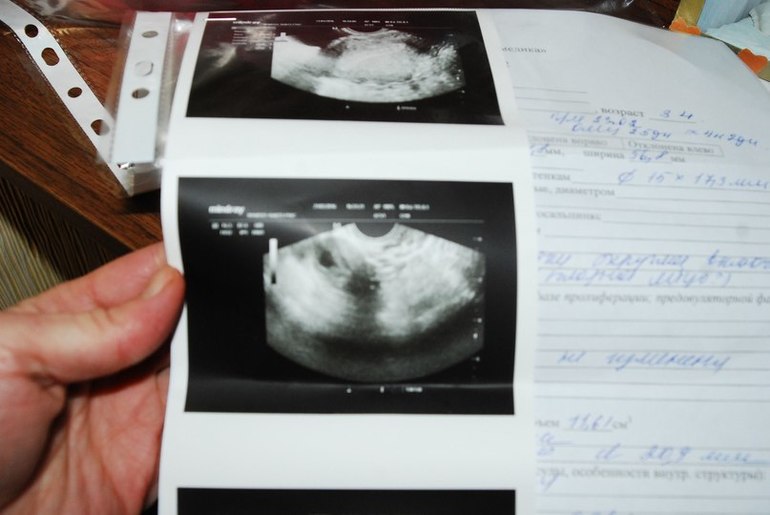

+на узи в 3-4 недельки одно яйцо было четко и под вопросом миома?!!!!

Подруге рассказала,она говорит что ее двойняшки тоже в 4 недельки были 1п.я и 1 миома....А в недель уже миома стала ребетенком)Сижу как на иголках...жду апрель месяц,чтоб сходить еще раз на узи)))

А еще в инете смотрю фото миомы в матке...она должна быть светлей,не такая темная.Сейчас скину 2 фотографии....одна моя в 3-4 недельки бер,а второе фото с инета...там плодное яйцо и миома.

что думаете????